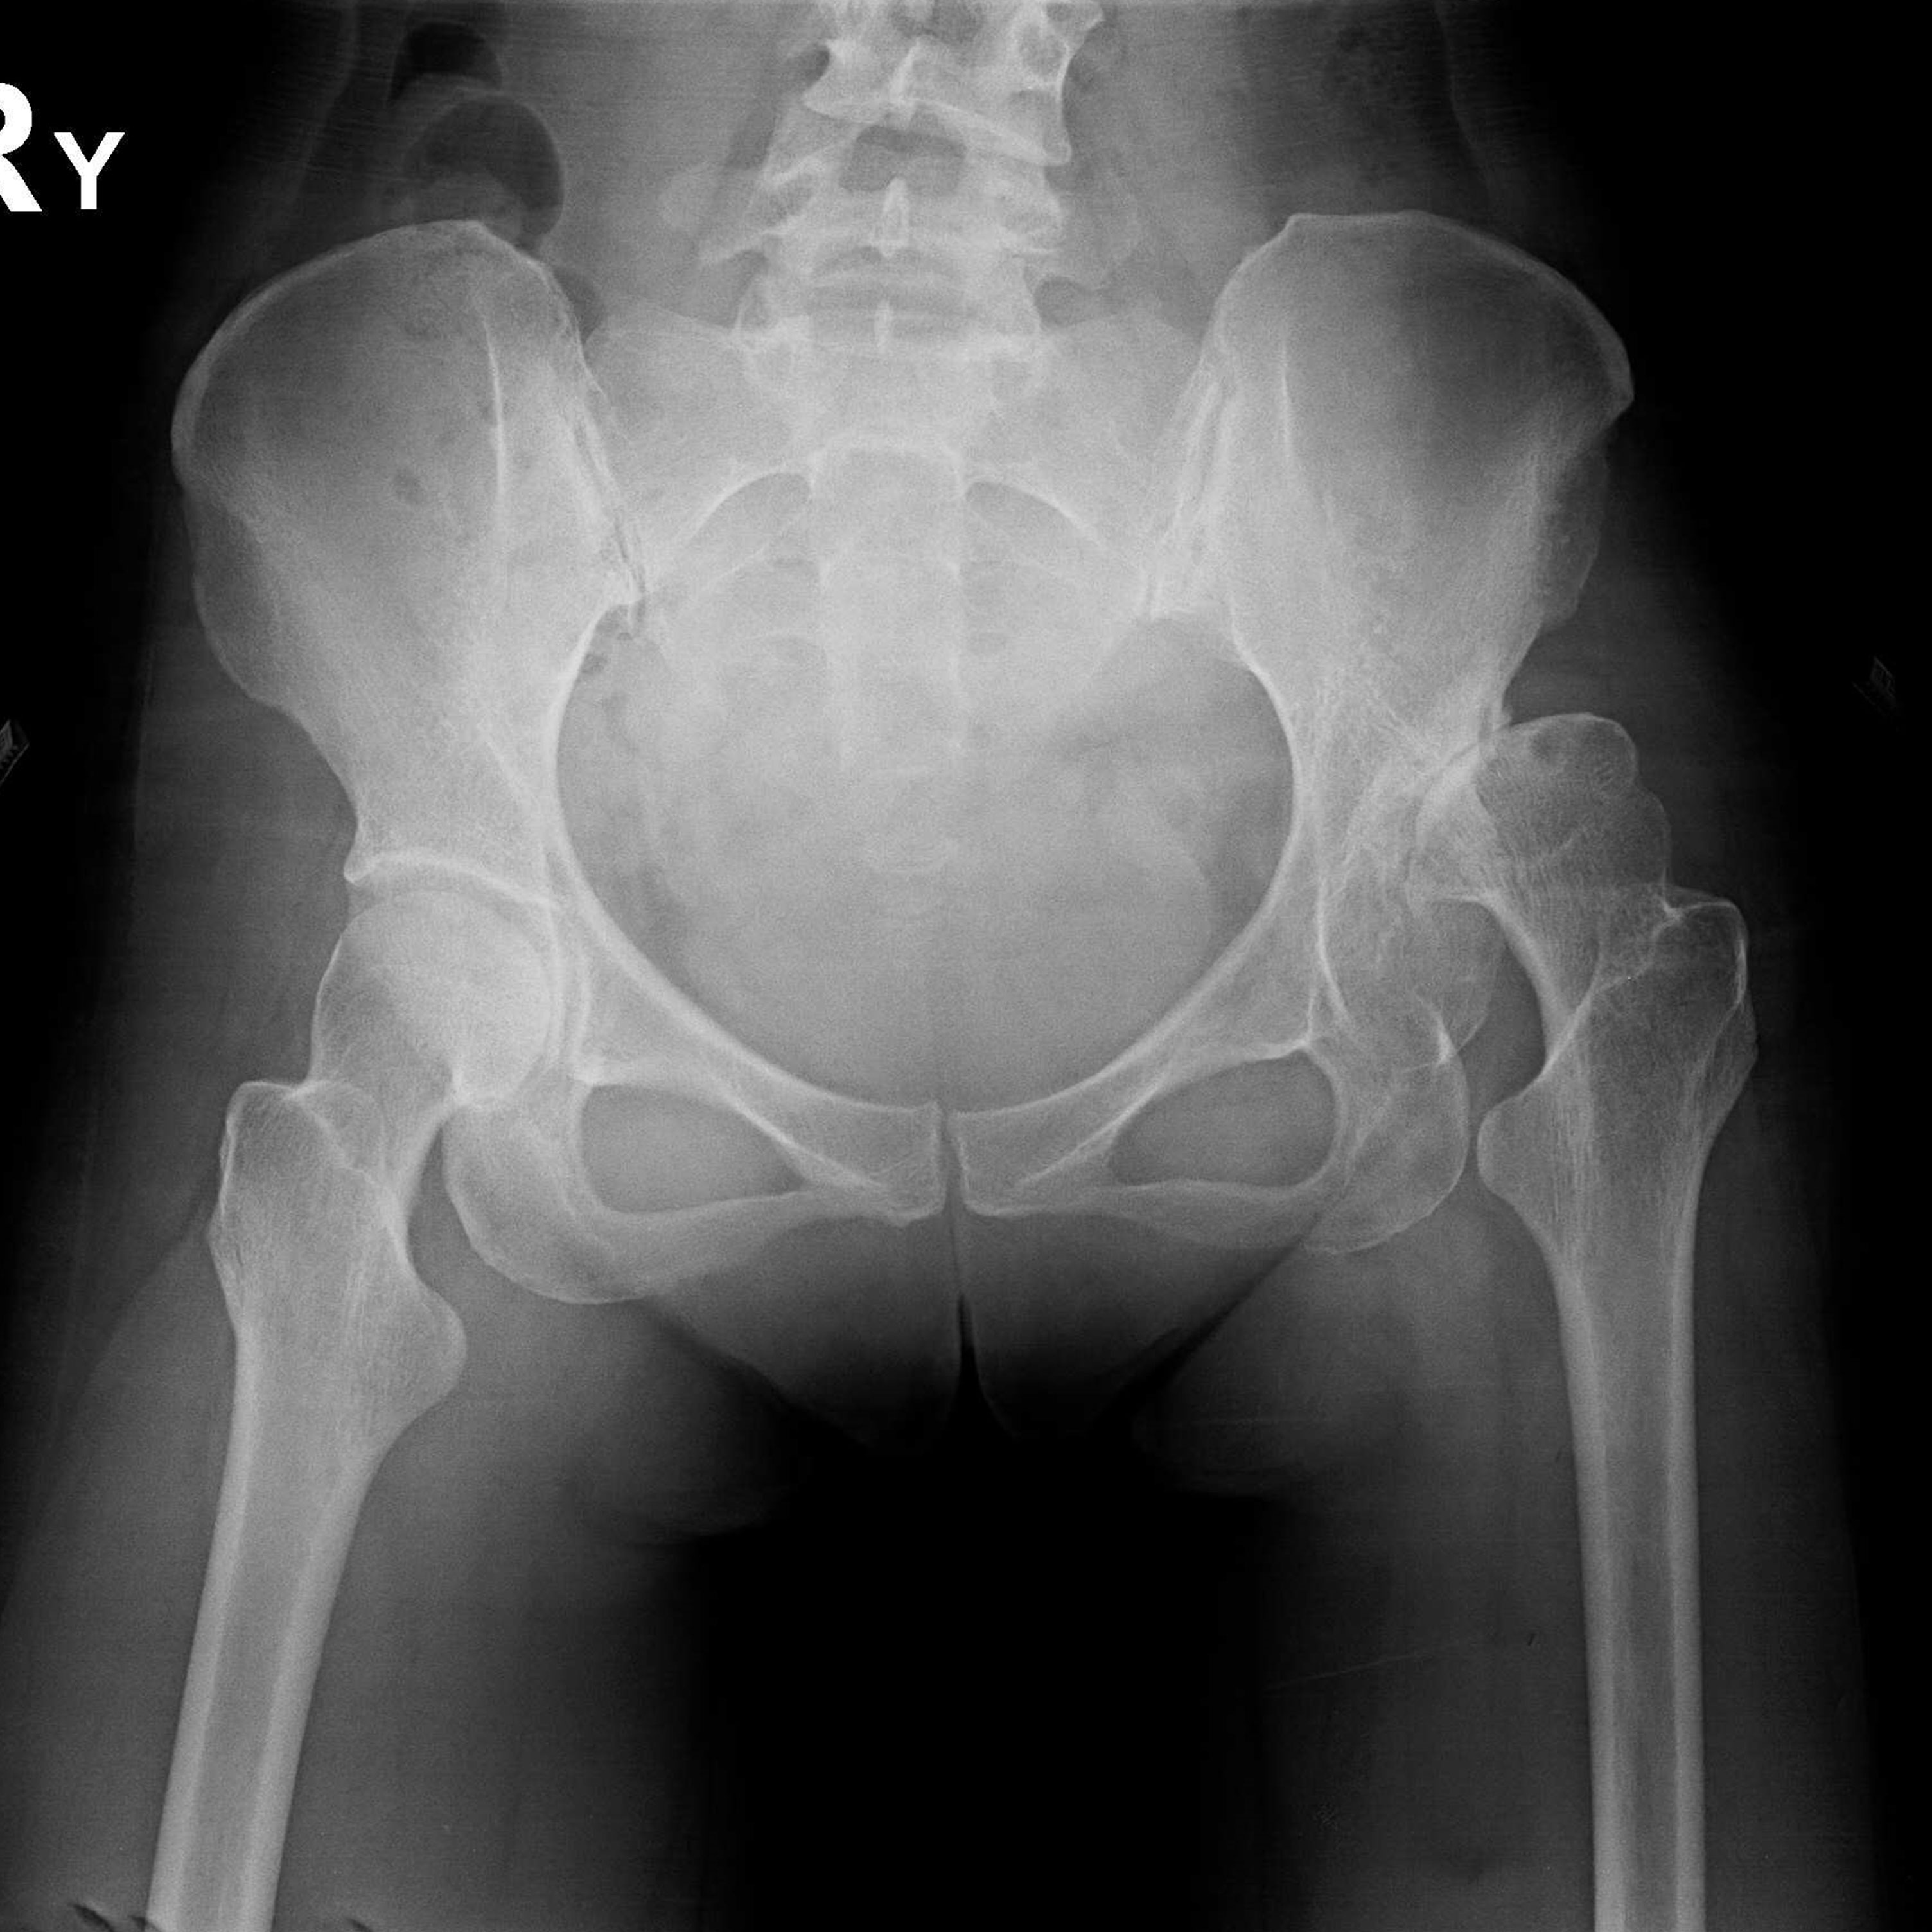

傳統髖關節置換 首頁 案例分享 髖關節手術 傳統髖關節置換 54歲蔡先生退化性關節炎 術前 術後 張女士 51歲 退化性關節炎(DDH先天發育不全 CROWE TYPE 2) 術前 術後 38歲林先生 退化性關節炎 術前 術後 72歲謝女士 退化性關節炎 術前 術後 71歲 謬女士 骨股頭壞死 術前 術後 50歲 郭先生骨股頭壞死 術前 術後 80歲 盧先生骨股頭壞死 術前 術後 林先生 37歲 術前 術後 邱女士 51歲 術前 術後 張女士 50歲 術前 術後